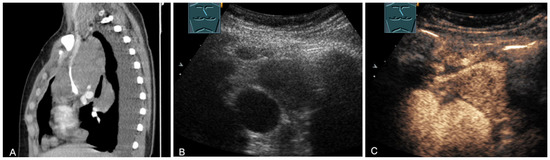

2.5. Solid and Cystic Primary Tumors

The spectrum of primary mediastinal masses includes a heterogeneous group of benign and malignant pathologies [28,31,36]. Benign primary mediastinal masses include congenital cysts (Figure 14), lipomas, thyroid tissue (Figure 15), benign thymomas, thymic residues, scar tissue, ganglioneuromas (Figure 16), schwannomas (Figure 17), and giant cell tumors (Figure 18) [28,31,36].

Figure 14.

A cystic mediastinal mass on CT (provided by Prof. Dr. Andreas H. Mahnken, Marburg, Germany) (A), B-mode US (B), and CEUS (C), surgically confirmed as a mediastinally located bronchogenic cyst.

Figure 16.

A young patient with tumor formation in the paravertebral mediastinum on CT (provided by Prof. Dr. Andreas H. Mahnken, Marburg, Germany) (A), B-mode US (B), and CEUS (C), surgically confirmed as ganglioneuroma.

Figure 17.

A young patient with tumor formation in the paravertebral mediastinum on CT (provided by Prof. Dr. Andreas H. Mahnken, Marburg, Germany) (A), B-mode US (B), and CEUS (C), surgically confirmed as schwannoma.